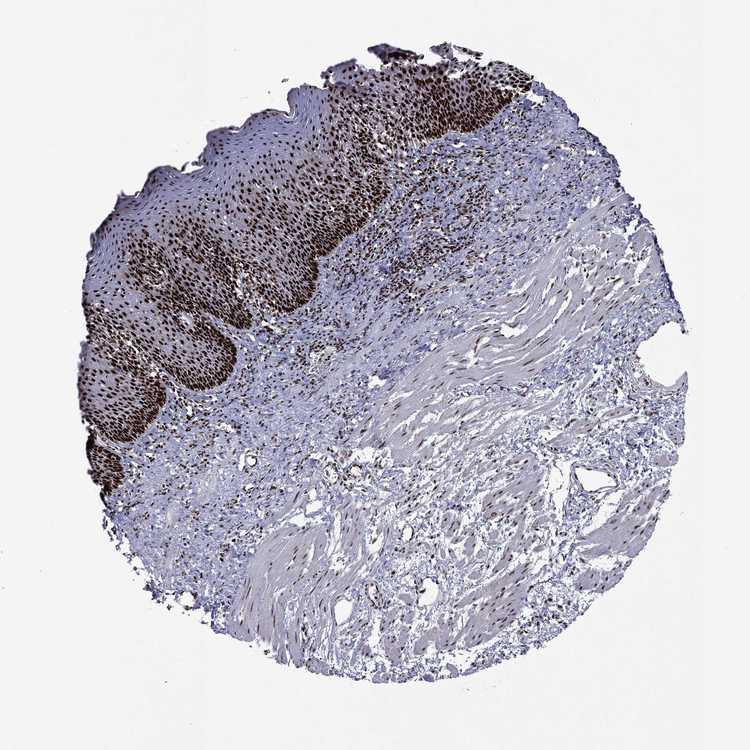

ESOPHAGUS - Antibody stainingi

Antibody staining in the annotated cell types in the current human tissue is reported as not detected, low, medium, or high, based on conventional immunohistochemistry profiling in selected tissues. This score is based on the combination of the staining intensity and fraction of stained cells.

Each image is clickable and will lead to virtual microscopy that enables deeper exploration of all samples and also displays staining intensity scores, fraction scores and subcellular localization as well as patient and tissue information for each sample.

Antibody HPA006714Antibody CAB079946Antibody CAB079947

Squamous epithelial cells HighHighHigh